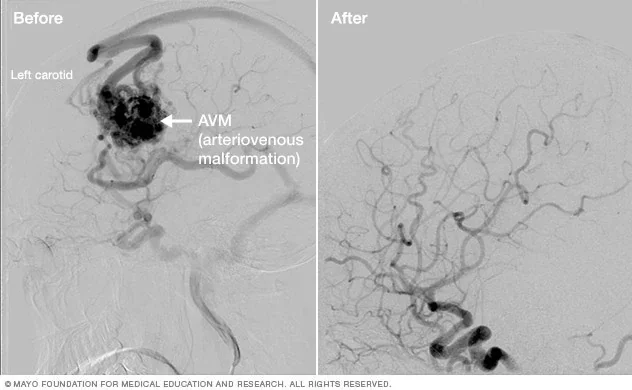

Patient selection relies on strict criteria, including lesion count and volume, yet current clinical guidelines are evolving to manage higher numbers of metastases.

Outcomes are often latent, with benign tumors shrinking over months or years post-exposure.

Historically, the evolution of brain tumor management has tracked with the miniaturization and accuracy of radiation delivery. Stereotactic radiosurgery has shifted from a novel intervention to a standard pillar of oncology, replacing whole-brain radiation in many contexts to preserve cognitive function and minimize collateral tissue damage. The current discourse within medical journals focuses not on whether SRS works, but on the optimization of fractionation protocols and the integration of salvage treatments for metastatic failure. The 90% deficit suggests that the future of the field is less about finding new physics and more about solving the geometry of healthcare access.